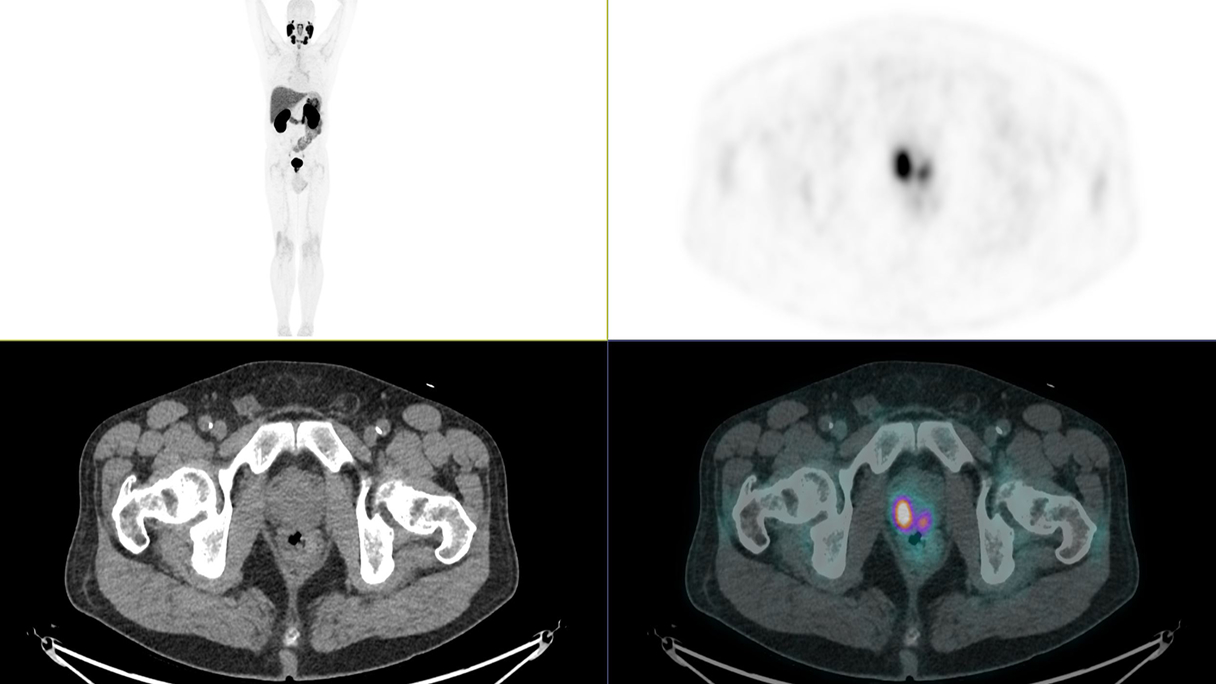

Fifty shades of grey

Caso condiviso da Marcello De Santis

Casi clinici

Scopri come le tecnologie di imaging più innovative di GE HealthCare hanno giocato un ruolo chiave nella diagnosi di condizioni cardiache complesse.